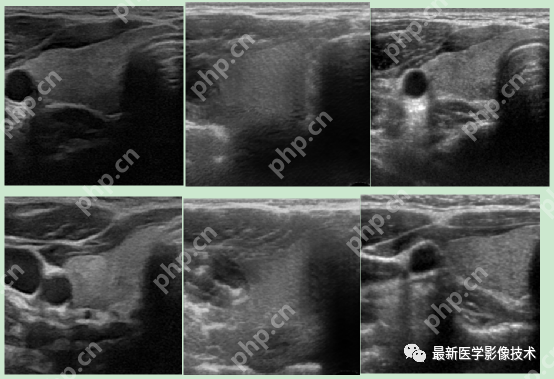

6、测试集部分生成结果

左图为低质量图像,右图为生成的高质量图像。